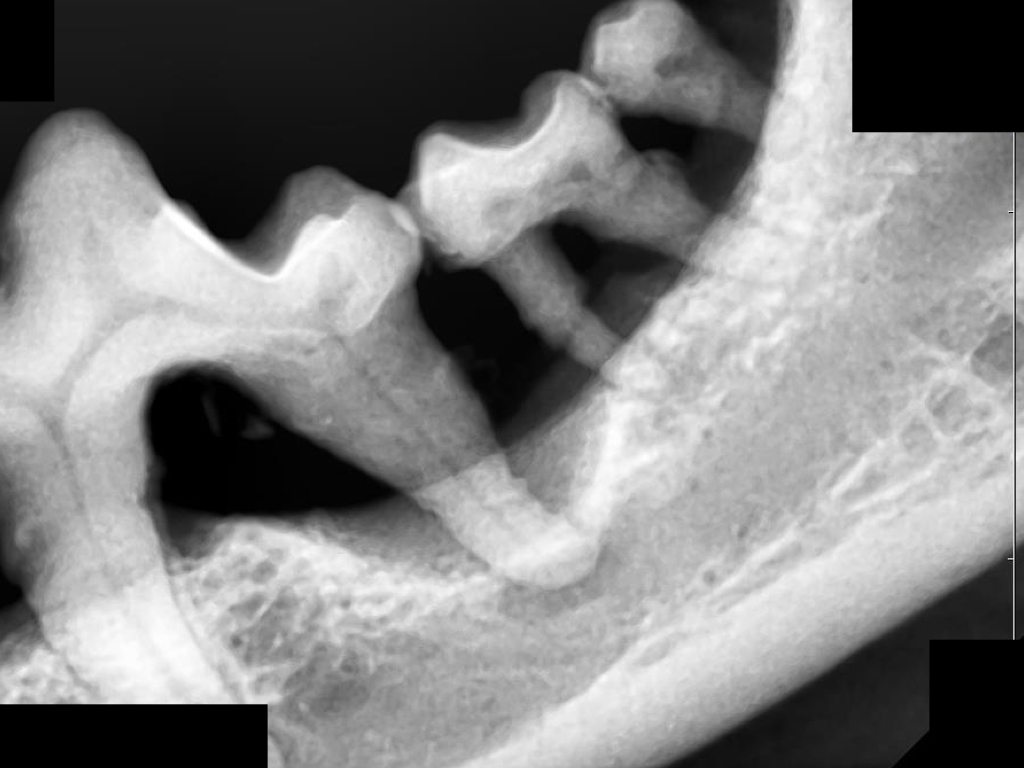

下の写真を見てみましょう。

左下顎の第四前臼歯から第三後臼歯にかけて、歯根や歯根の分岐部が見えています。

歯科レントゲンを撮影してみるとやはり歯槽骨の融解が進んでいました。

この歯はアタッチメントロスが50%以上、多根歯でステージⅢの根分岐病変を認めたため重度歯周病として抜歯が適応となります。